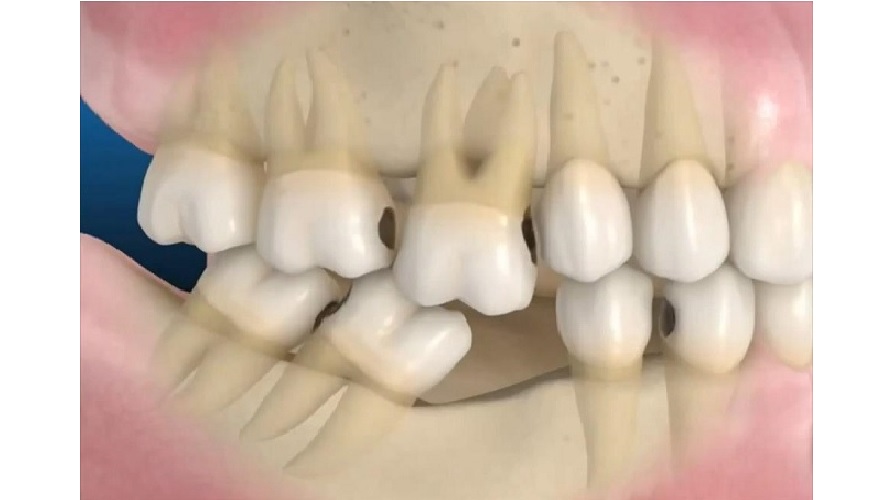

Răng khi bị mất, các bác sĩ luôn khuyên nên phục hồi ngay bằng phương pháp cấy trực tiếp trụ Implant vào xương hàm để tránh tình trạng tiêu xương. Nguyên nhân vì răng khi bị mất sẽ tạo khoảng trống trên hàm. Khoảng trống răng không còn chức năng ăn nhai. Vì thế theo cơ chế đào thải của cơ thể vùng xương sẽ bị tiêu. Tiêu xương khiến xương hàm biến dạng, da nhăn cũng như dễ gây rối loạn khớp cắn. Không chỉ gây mất thẩm mỹ mà còn gây tốn kém về sau khi phục hình.

Bảo tồn răng thật xung quanh

So với phương pháp làm cầu răng giả phải mài răng hai bên làm trụ đỡ và đeo hàm giả tháo lắp những móc kim loại có thể ảnh hưởng đến những răng thật xung quanh, thì phương pháp trồng răng Implant được phát triển hơn để không phải tác động gì đến những răng xung quanh.

Giải pháp thay thế lúc này cho lứa tuổi 14 – 16 là sử dụng hàm giữ khoảng để giữ nguyên khoảng trống mất răng. Từ đó giúp các răng trên cung hàm không bị xô lệch theo thời gian. Cần sử dụng khí cụ này cho đến khi trẻ đủ tuổi để cấy ghép Implant.

- Cố định khoảng trống mất răng. Giữ kích thước dọc và kích thước ngang để ngăn ngừa biến chứng xô lệch hàm.

- Giúp răng đối diện răng mất ở hàm còn lại không bị trồi lên quá mức khi hoạt động ăn nhai lâu ngày.

- Phòng ngừa nguy cơ lệch hàm, sai khớp cắn do xương hàm phát triển sai lệch khi mất răng.